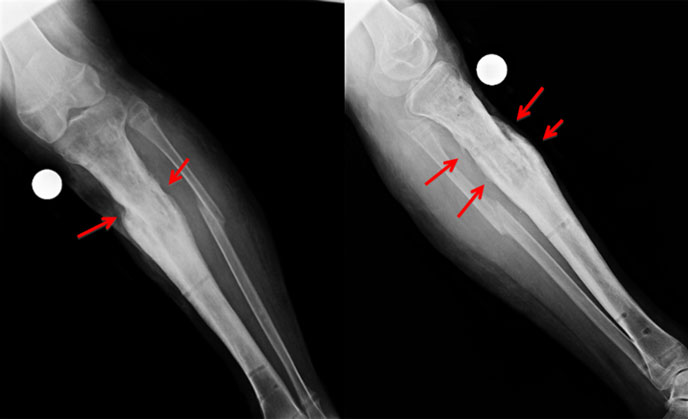

| After fixator removal |

| The x-rays right after fixator removal. The callus is well seen (red arrow) bypassing &bridging the nonunion site. |